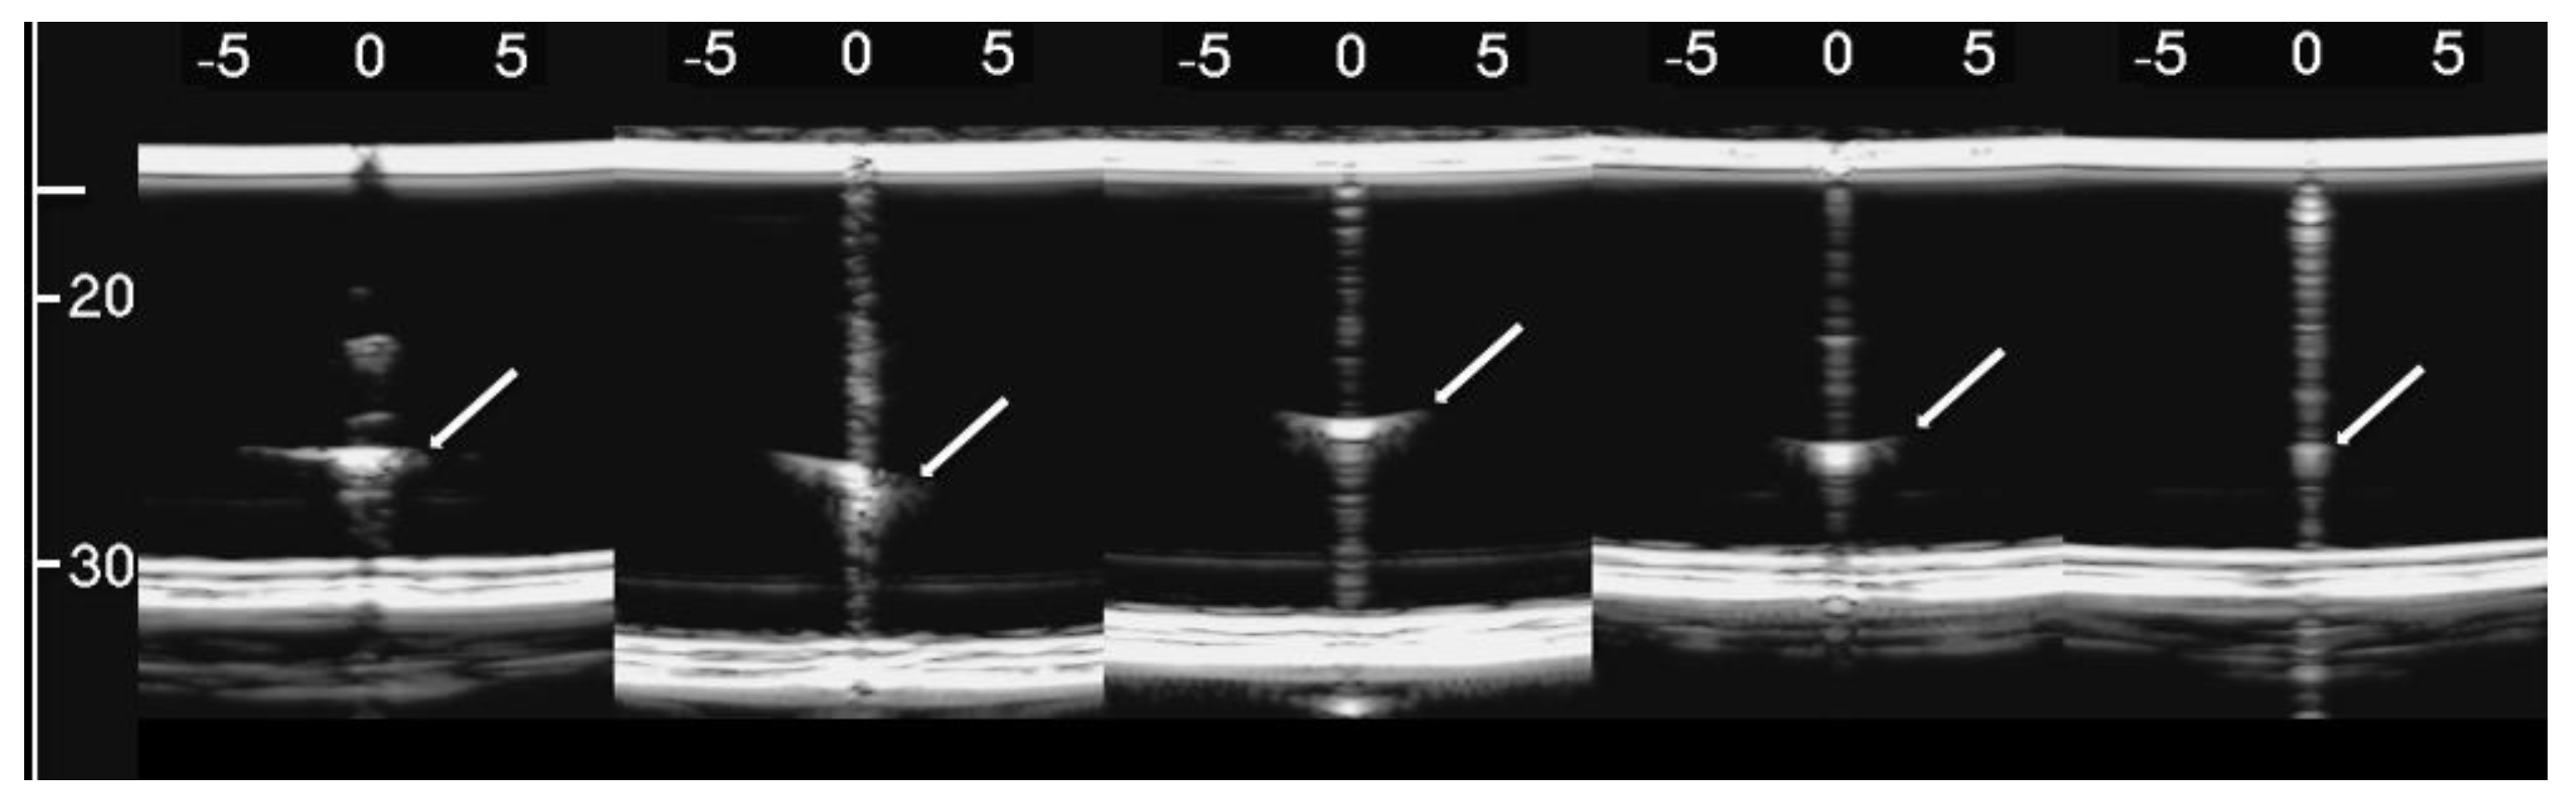

The simulated septa, which were obtained by using the pair of external moulds printed by setting the spatial resolution of the 3D printer to 0.1 mm, were first analysed. The first four images in Figure 10 from left to right show the artifacts which were obtained on four different simulated septa with smooth lateral surfaces and with thicknesses equal to 1.2, 0.8, 0.6, and 0.4 mm. It is worth noting that in this case, the vertical artifacts begin just below the upper polyethylene film. The septa with a thickness equal to 0.8, 0.6, and 0.4 mm provided modulated artifacts even though the 0.8 mm septum showed a slightly confused modulation. However, Figure 10 also shows an unexpected acoustic sign which is not observed on US lung images. The whiter sign, which is observed within the modulation of the three artifacts, is given by the reflection of the lower polyethylene film. The bottom of the septa gives rise to a reflection which is clearly highlighted in Figure 10, and this experimental result is not consistent with the observations of the physicians. Therefore, the simulated septa, which were obtained by using the pair of external moulds printed by setting the spatial resolution of the 3D printer to 0.280 mm, were also analysed. The vertical artifact which was obtained on a 0.4 mm septum with rough lateral surfaces is shown in the last image on the right of Figure 10. The strong reflection of the bottom of the septum is still perceivable, but this time, it is partially masked within the vertical artifact, and the latter is closer to the artifacts which are observed on US pulmonary images. Modulated vertical artifacts were obtained, and a correlation with the thickness of the septa emerges again, as expected by physicians.

Figure 10. From left to right: the first four images show the vertical artifacts which were obtained with agar septa having smoother lateral surfaces and thickness equal to 1.2, 0.8, 0.6, and 0.4 mm. The last image on the right shows the vertical artifact which was obtained with an agar septum with rough lateral surfaces and a thickness equal to 0.4 mm. The two thick white lines at the top and at the bottom of every image represent the reflection of the upper polyethylene film and its replica, respectively. The arrows indicate the reflection of the lower polyethylene film.